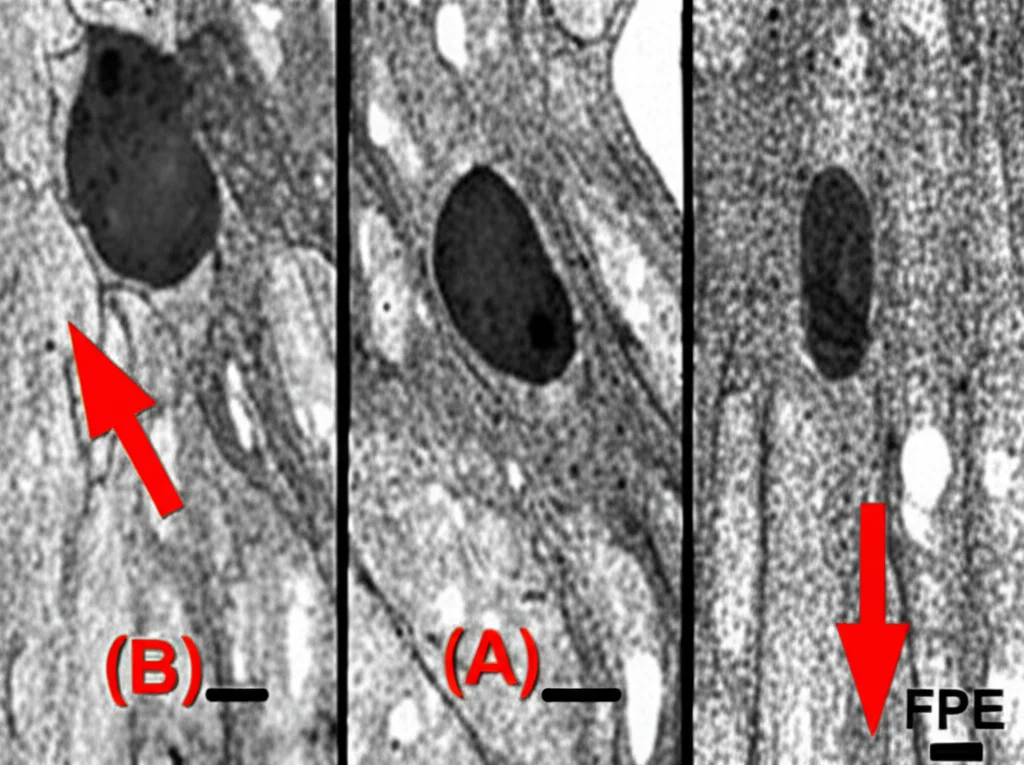

Ora, cosa succede quando questi podociti si danneggiano? Una delle alterazioni più caratteristiche che vediamo al microscopio elettronico è la cosiddetta fusione dei processi podocitari (Foot Process Effacement – FPE). In pratica, questi “piedini” perdono la loro forma definita, si appiattiscono, si allargano e si fondono tra loro, coprendo la membrana basale glomerulare. Questo “appiattimento” aumenta la permeabilità del filtro, facendo passare proteine che non dovrebbero. È un po’ come se le maglie di un setaccio si allargassero troppo.

La chiave del nostro lavoro è stata classificare i pazienti in base all’estensione della FPE osservata al microscopio elettronico. Abbiamo definito:

- FPE segmentale: se la fusione interessava meno del 50% della superficie capillare osservata.

- FPE estesa: se la fusione interessava il 50% o più della superficie.